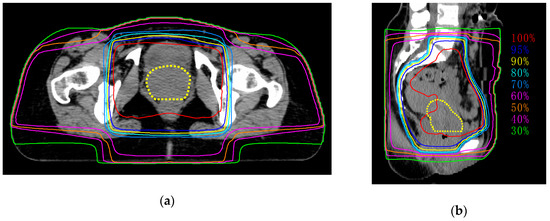

2.2. Treatment

| EBRT dose | 55.6 Gy/29 fr. |

| IGBT dose | 24 Gy/4 fr. |